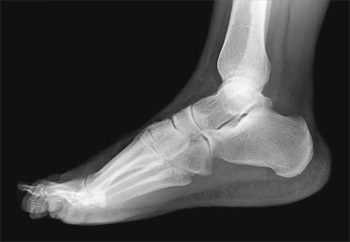

Рентген голеностопного сустава

Востребованным диагностическим методом при травмах и заболеваниях ног в течение многих десятилетий остается рентген голеностопного сустава.

Исследование выполняется при помощи рентгеновского излучения, которое пропускают через нижнюю конечность.

В результате на чувствительном экране появляется изображение костей, формирующих сустав и стопу.

По характеру деформаций костных структур и другим признакам, отображенным на снимках, определяется диагноз и назначается оптимальный вид лечения.

• Что показывает рентген голеностопного сустава?

На снимке опытный диагност легко различает:

• трещины или переломы костей;

• вывихи сустава;

• наличие новообразований;

• признаки воспалительных процессов;

• нарушения костной структуры;

• кальциноз сосудов нижней конечности;

• некротический процесс мягких тканей;

• наличие пяточной шпоры;

• врожденные или приобретенные деформации костей.